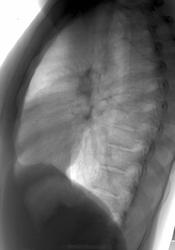

Молодой человек 30 лет. Проводил ц ФГ в 2010 году, после чего был направлен на дообследование (КТ). Сейчас пришел на контроль, протокол КТ предстваил лично.

От бокового снимка отказался...увы. Что скажете?

Шаровидная тень: в S4 в/доли слева (1 случай) и S10 н/доли справа (2 случай)

Татьяна Валентиновна, асолютно согласен. что основной рентгенологический признак - шаровидные тенеобразования, но...достаточно ли они "шаровидны" и достаточно ли однородны....+молодой, в общем то возраст, + отсутствие существенных жалоб. Конечно, смущает тот факт, что это не первые их ФГ (но у меня то они впервыеwink). Опять же - в С10 (скрывается за тенью печени), в С4 слева (не факт, что раньше было перекрыто левым краем сердца) и, как следствие - не были обнаружены.

Внутрилегочная секвестрация или артериовенозная мальформация.

..... артериовенозная мальформация.

Она самая))). Да, оба случая подтверждены на КТ.

Нечего сказать. Вспомнился мой же №5'). из вопросной ветки... С одной стороны патология видна и на обзорных (в обоих случаях). С другой - с учётом отсутствия жалоб, клиники диф. ряд получился бы немалым. Приоритет диагностики в отношении а/в мальформаций, конечно, у КТ/МСКТ, но гарантирую, что во втором случае с парнем поставил бы (если бы не забыл по такой Rg-картине) эту нозологию далеко не в первых числах...